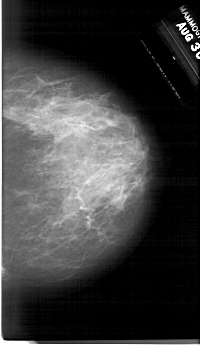

A_1761_1.RIGHT_CC

RIGHT_CC LINES 6256 PIXELS_PER_LINE 3601 BITS_PER_PIXEL 12 RESOLUTION 43.5 NON_OVERLAY